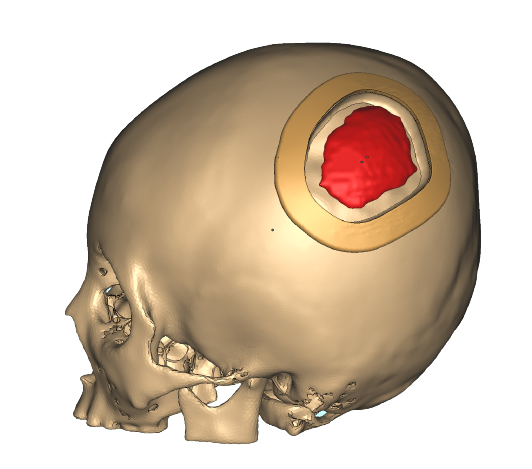

医療

医療